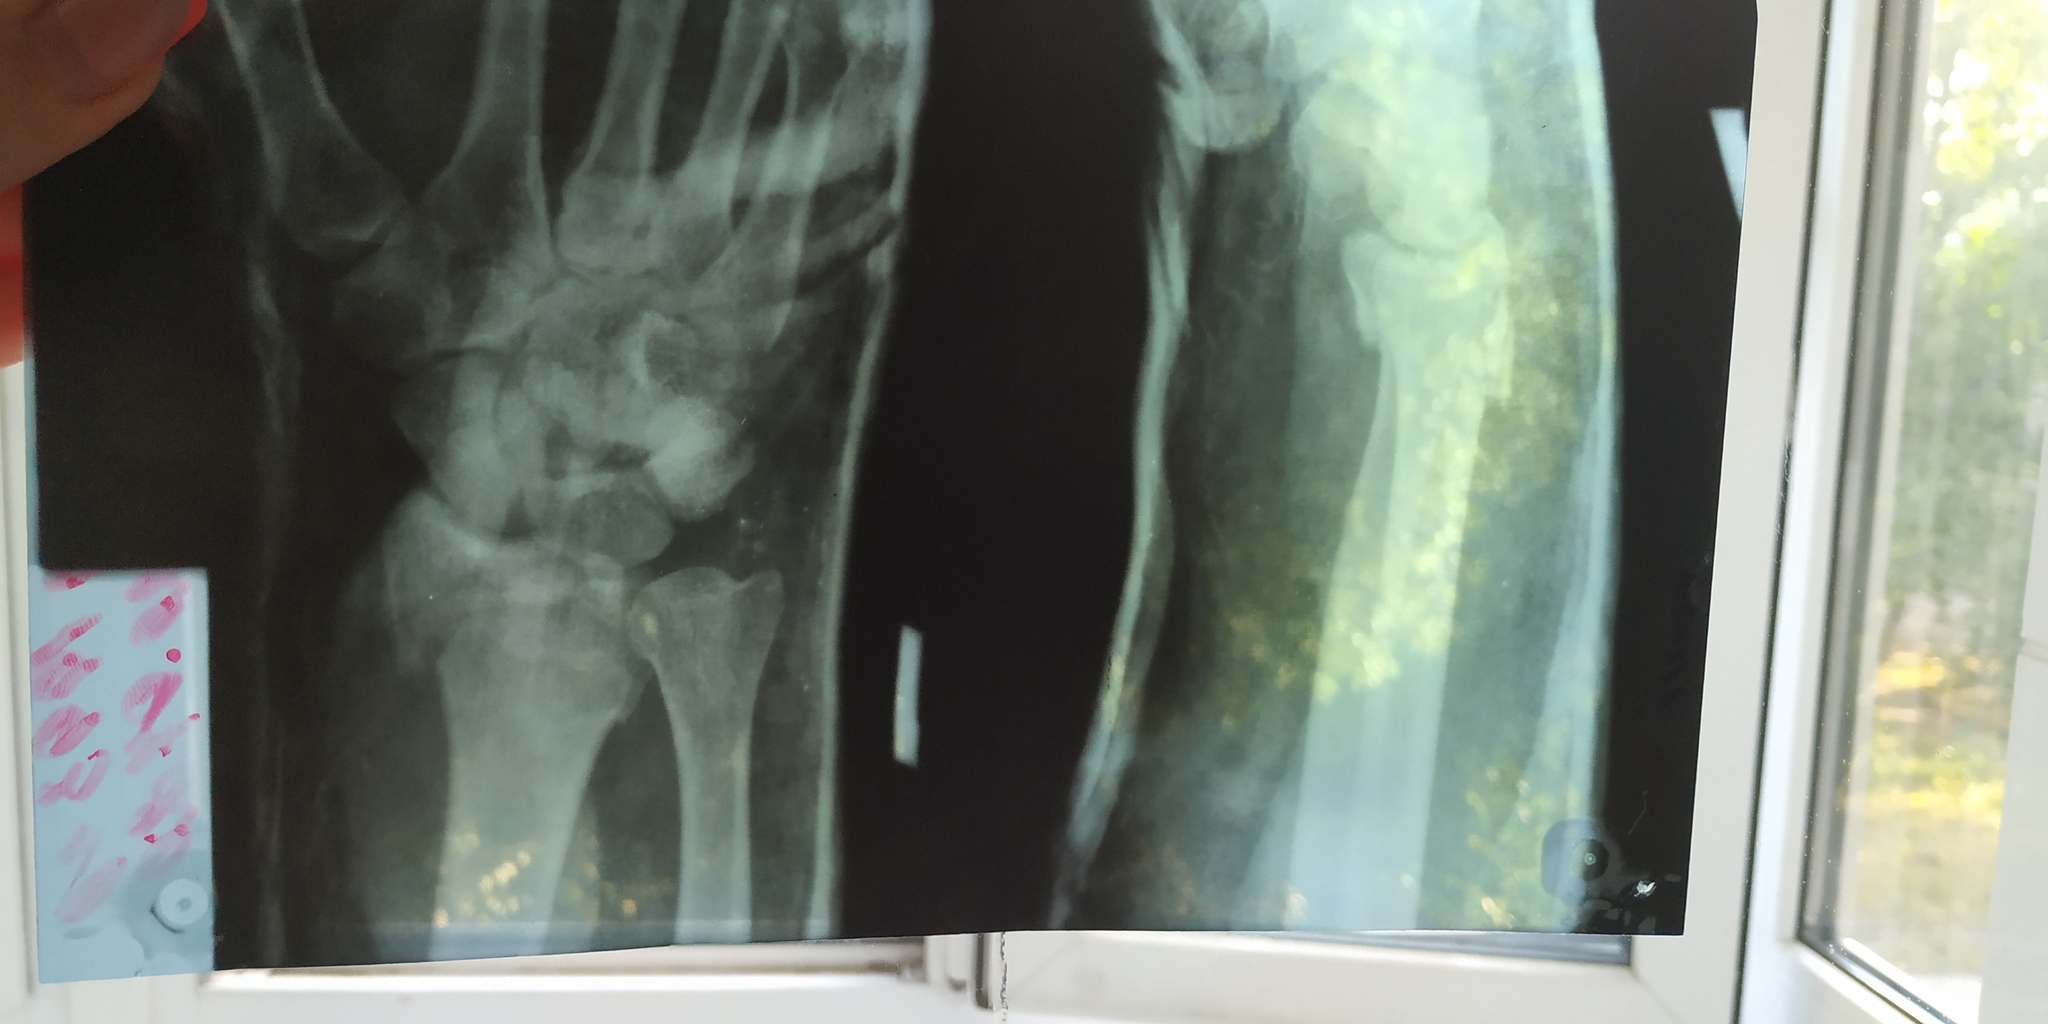

15.07 в прекрасном настроении мы всей семьей рванули на дачу и муж полез на злосчастную абрикосу, чтобы ее потрусить. Потрусил хорошо, но когда слазил - уцепился за сук двумя руками, а сук обломался и муж упал. Упал буквально с метра высоты, но очень неудачно - сломал левую руку. Как сказали врачи в травмпункте - закрытый сложный перелом со смещением и ушибом. Рентген прилагаю - это 15.07, когда сломал руку.

Мы приехали в больницу, где ему под общим наркозом вправили кости. Это рентген также 15.07, после вправления.

29.07 сделали еще один снимок, забрали только 30.07. Врач сказал, что все хорошо, но тот кто делал рентген сказал,что кость сместилась и нужно ставить аппарат Илизарова. Рентген прилагаю.